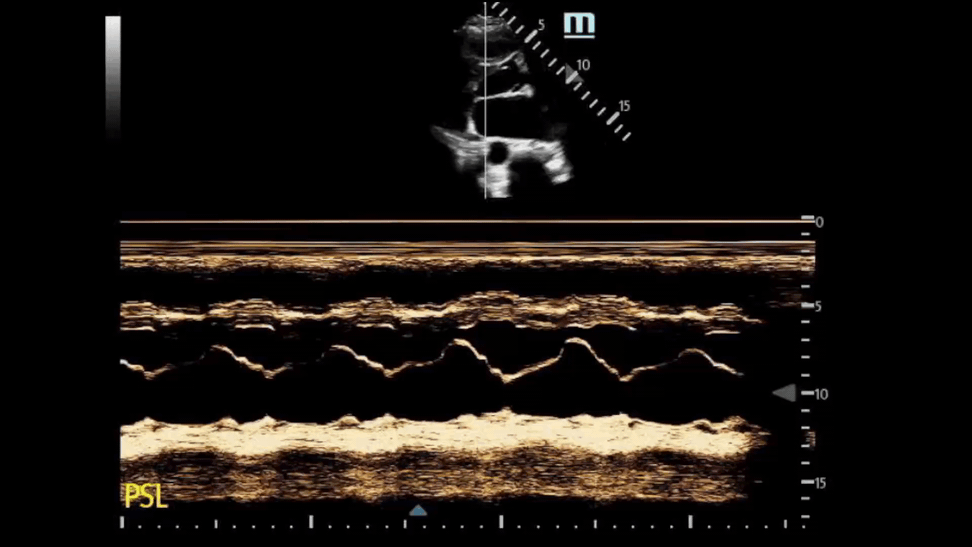

Finding #3: Systolic anterior motion (SAM) of mitral valve

View: PSL View with M Mode, place axis as if you were measuring EPSS at tip of mitral valve

• During systole, the mitral valve should be closed. But in HCM, the mitral valves actually move anteriorly during systole. This can be visualized by using M-Mode.

• This finding used to be pathognomonic for HCM but recent studies have found that only 25-50% of HCM patients with SAM have LVOTO

• The time the mitral valve is in contact with the septum can classify disease severity:

• Mild: brief SAM without septal contact

• Moderate: septal contact is < ⅓ of systolic period

• Severe: septal contact is > ⅓ of systolic period

• Notably, you will also see mitral regurgitation on ultrasound as well

This is the M Mode on the PSL View of a normal heart. Notice how you see the opening of the mitral valve in diastole (almost touches the septum) and the closing of the mitral valve in systole.

This is the M Mode on the PSL View of a heart with HCM. Notice how you see the opening of the mitral valve in diastole (valve touches the septum), BUT you see the mitral valve moving anterior during systole (arrows).

This is another example of SAM on a HCM patient.

We used M Mode on the mitral valve and did not see SAM.